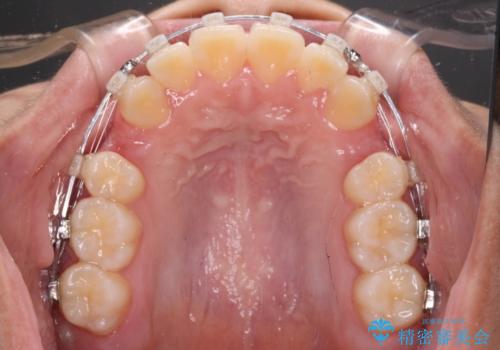

- 矯正装置

- クリアブラケット

検査を行った結果、上顎骨の横幅が相対的に狭いことが分かり、叢生が強いことから、急速拡大装置にて上顎骨を側方に拡大することで、叢生の解消と奥歯の咬み合わせ改善を図ることとしました。

一般的には上下左右の第一小臼歯4本を抜歯する必要がありますが、拡大量によっては非抜歯矯正の適用となる可能性があるため、まずは非抜歯矯正で治療を開始し、抜歯が必要と判断された時点で速やかに4本抜歯を行うこととしました。